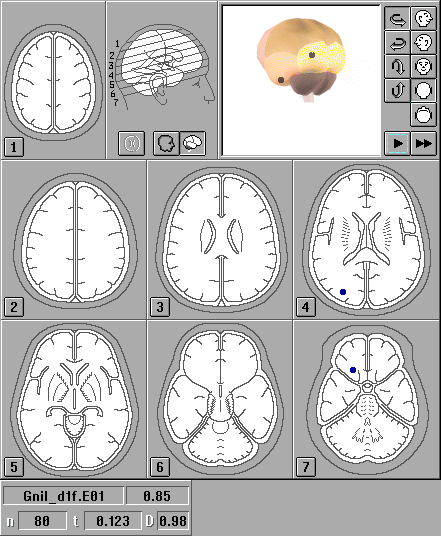

Расположение источника (генератора) ЗВП и место регистрации наибольшего значения потенциала на поверхности головы нередко не совпадали, что некоторыми авторами объясняется различной ориентацией источников ЗВП и наличием у мозга, его оболочек и ликвора свойств объемного проводника [1,2,9]. Для уточнения данных топографического картирования использовали метод трехмерной локализации дипольных источников ЗВП, предназначенный для компьютерного моделирования расположения доминирующих центров биоэлектрической активности в структурах мозга [1,2,9,16,17]. Трехмерная локализация источников ЗВП осуществлялась с помощью компьютерной программы "Брейнлок 5.0" (автор Коптелов Ю.М.). В качестве входной информации, как и для топографического картирования, использовали многоканальную запись ЗВП. Дипольные источники ЗВП изображались на ортогональных проекциях головы в виде ''стрелок'' с основанием в центре вычисленного диполя. ''Стрелки'' направлены от "минуса" диполя к его "плюсу". Также источники выводились на семь схематических изображений срезов головного мозга, сделанных в орбито-миотальной проекции. Для улучшения объемного представления источники изображались внутри трехмерной вращающейся модели головного мозга. При наличии файлов магнитно-резонансной томографии локализация проводилась с учетом реальной топографии структур мозга пациента.

Рис.2. Локализация источников вспышечных ЗВП в норме: ортогональные проекции

Рис.3. Локализация источников вспышечных ЗВП в норме: послойные изображения

Рис.4. Локализация источников вспышечных ЗВП в норме: МР-томографические изображения